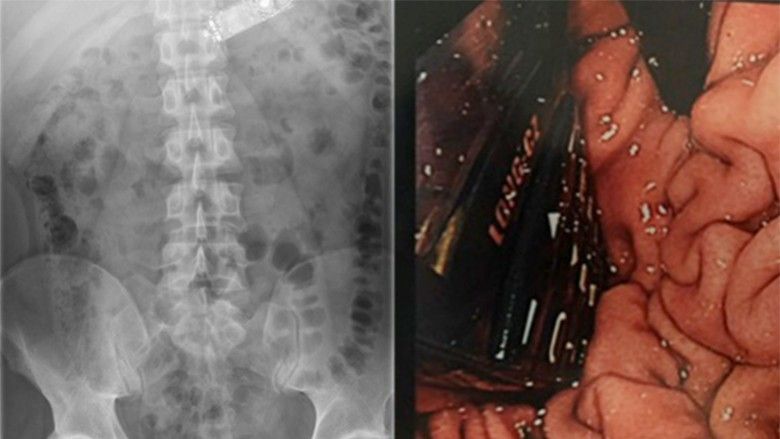

Duke parë se gjendja tij po përkeqësohet, është dërguar në Tallaght Hospitale të Dublinit, ku i është nënshtruar fotografimit me rreze X.

Pajisjen e përpirë, mjekët kanë provuar t’ia nxjerrin me disa grepa, por ka qenë e pamundur, andaj e kanë operuar.